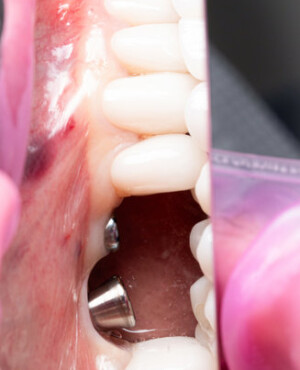

După extracția dentară, în intervalul de 6-12 luni, osul alveolar suferă un proces natural de remodelare, ceea ce conduce la scăderea volumului osos prin rezorbție. De aceea, inserția implantului dentar este ideală imediat după extracție sau, cel târziu, în primele 3-4 luni după aceasta.Scopul procedurilor de adiție osoasă este refacerea fundației osoase necesare pentru stabilizarea corectă a implantului dentar. Pentru ca un implant să reziste în timp la forțele masticatorii, este nevoie de o bază osoasă solidă și sănătoasă.

Aditia gingivală este o procedură chirurgicală ce corectează diverse probleme estetice și funcționale, cum ar fi recesiunea gingivală. În implantologia modernă, aditia de țesut moale este utilizată aproape în fiecare intervenție de inserție a implantului dentar pentru a asigura un aspect estetic natural și o bună integrare a implantului în cavitatea bucală.